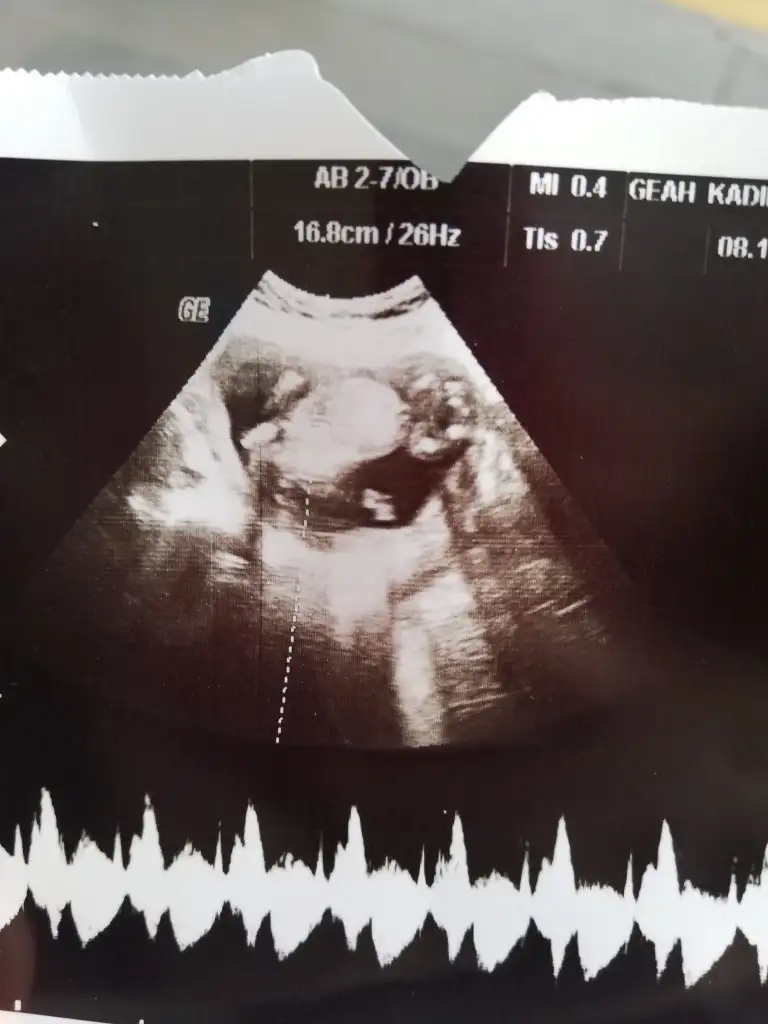

İyi yapmışsın canım ay bi de değişiyormuş cinsiyeti bi değişiklik bişey olursa bize de haber ver olur mu